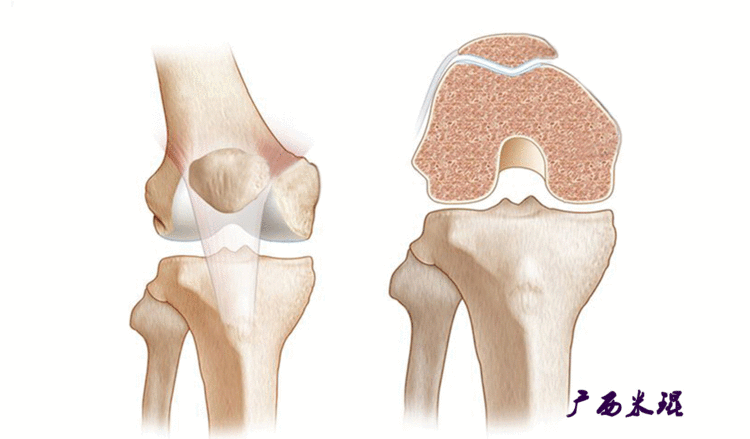

说到髌骨脱位,首先就要了解髌骨,髌骨是人体最大的籽骨,倒三角状位于膝关节前方,它的上缘与股四头肌腱相连,下缘通过髌韧带止于胫骨结节上,两侧为股四头肌扩张部,髌骨后方的凸面为光滑的关节面,与股骨下端内外髁之间的滑车凹面关节面形成关节。尽管股四头肌中的股直肌、股中间肌、股外侧肌的作用方向与髌韧带不在一条直线上,髌骨有向外突出的倾向,但因股内侧肌有向内上方牵拉作用力而使髌骨维持在正常位置。